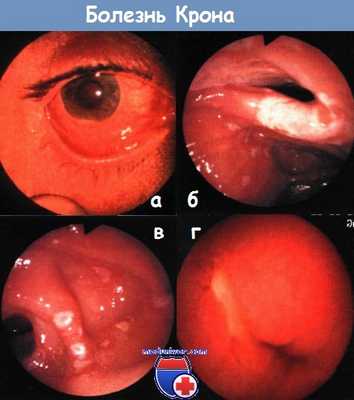

а - болезнь Крона: утолщение концевых фаланг пальцев ног

б - болезнь Крона: афтозный стоматит

в - артропатия коленных суставов — выпот в супрапателлярной сумке

г - рентгенологический снимок коленного сустава пациента с болезнью Крона